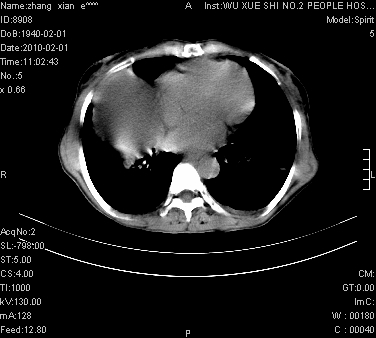

标题: CT24434:70岁 女 腹胀,腹水原因待查 [打印本页]

标题: CT24434:70岁 女 腹胀,腹水原因待查

大量腹水,脾脏囊性占位,子宫颈占位,右侧腹股沟淋巴结肿大,建议+c,先查妇科。

腹盆腔大量积液,子宫增大,子宫颈增大外形不规则,内见低密度影,膀胱后壁显示不清,右腹股沟肿大淋巴结,脾脏囊性占位,子宫颈占位,子宫颈癌?建议增强。

子宫、宫颈占位?转移性腹水?肝性腹水?脾脏囊性占位,囊肿?血管瘤?淋巴瘤?

大量腹水,右肾、脾囊肿可能性大          考虑左侧附件区占位,建议增强